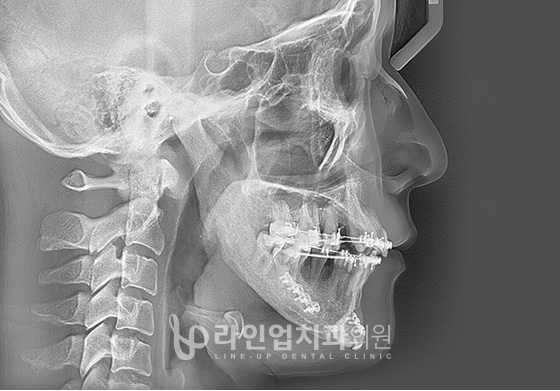

下颚手术方法

01

从后槽牙后面的颌骨开始到和骨关节之间进行切骨

02

根据手术计划移动位置

03

用金属板固定颌骨